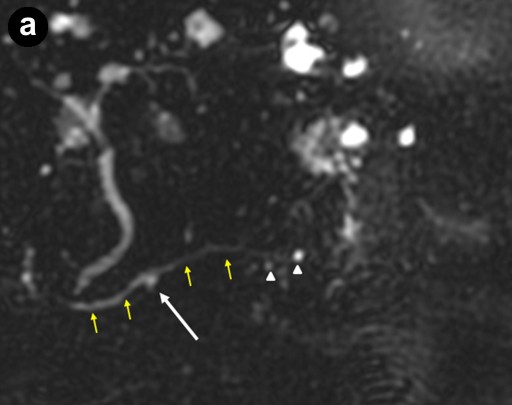

A 79-year-old asymptomatic women was found to have a serum CA 19-9 of 210 U/mL (reference range: 0-37 U/mL) during a general medical examination in 2000; the CEA level was 1.8 ng/mL (reference range: 0-5.0 ng/mL). They were done by her primary care physician because of a family history of breast and ovarian cancers. Computer tomography (CT) and magnetic resonance imaging cholangiopancreatography (MRCP) examinations in 2000, 2001, and 2002 from an outside facility reported stable small cysts at the head of the pancreas. The patient had never smoked or been an alcohol drinker. She had no history of pancreatitis or abdominal trauma. Her past medical history was significant for recurrent pneumonia, partial hysterectomy, and gastroesophageal reflux disease. Upon referral to our institution in 2003, MRCP demonstrated several subcentimeter pancreatic cysts in communication with a non-dilated pancreatic duct; endoscopic cholangiopancreatography (ERCP) revealed a subcentimeter cyst in the pancreatic head, communicating with the main pancreatic duct (Figure 1). No pancreatic abnormalities were seen on endoscopic ultrasound (EUS). High resolution CT of the chest showed bronchiectasis predominately in the right middle lobe and lingula consistent with Lady Windermere syndrome (Figure 2). In 2005, the patient was hospitalized several times with the diagnosis of "community acquired pneumonia." Repeat high resolution CT of the chest showed worsening of bronchiectasis with Mycobacterium avium-intracellulare complex-positive sputum cultures. The Mycobacterium avium-intracellulare complex infection was not treated because the positive cultures were thought to be due to colonization. In 2006, the patient was hospitalized again for pneumonia and triple therapy (rifampin, ethambutol, azithromycin) was started for Lady Windermere syndrome. Due to side effects, the therapy was discontinued after 3 months of treatment.

Figure 1. "Low-risk" branch duct intraductal papillary mucinous neoplasm. 3-D MRCP (a.) image shows several small cystic lesions (white arrow and arrowheads) projecting near the main pancreatic duct (yellow arrows). Subsequent sequential ERCP images (b., c.) show slow opacification of the cystic lesion in the pancreatic head (white arrows) with increasing contrast administration, corresponding to the cystic lesion identified on MRCP (a.: white arrow). Although a bridging duct or stalk was not well visualized, communication with the main pancreatic duct is inferred due to its opacification with contrast. Other cysts in the pancreatic tail are not seen possibly because of viscous mucin or papillary growth obstructing the ductal lumen. |